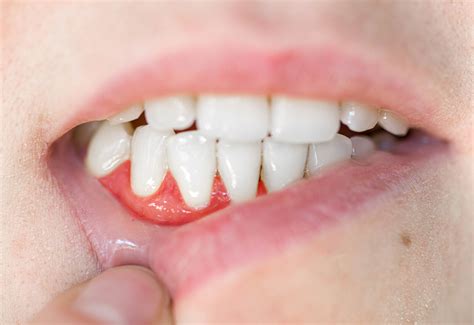

• Pain and swelling in the gums

• Redness and tenderness in the affected area